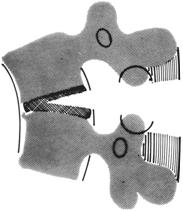

Выделяют несколько вариантов компрессионных переломов:

тип А – вертикальный перелом с повреждением обеих замыкательных пластинок.

Тип В – перелом с повреждением верхней замыкательной пластинки.

Тип С – перелом с повреждением нижней замыкательной пластинки.

Тип D – центральный перелом тела позвонка, захватывающий только переднюю колонну.

Рис. 1. Варианты компрессионных переломов позвонков по F.Denis

А - компрессионный перелом с повреждением обеих замыкательных пластинок тел позвонков,

В - компрессионный перелом с повреждением верхней замыкательной пластинки тела позвонка,

С - компрессионный перелом с повреждением нижней замыкательной пластинки тела позвонка,

Д - компрессионный перелом средней части тела позвонка